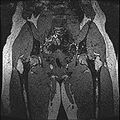

• Generated label maps of knee and hip structures.